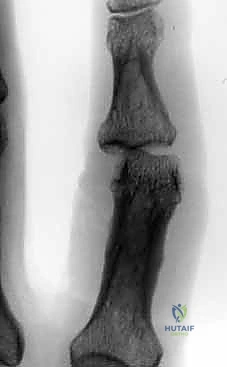

الحالة الأولى: كسر خلع ظهري مفتت بشدة

- قبل الجراحة: تظهر الأشعة خلعاً تاماً للمفصل مع تفتت شديد في قاعدة السلامية الوسطى.